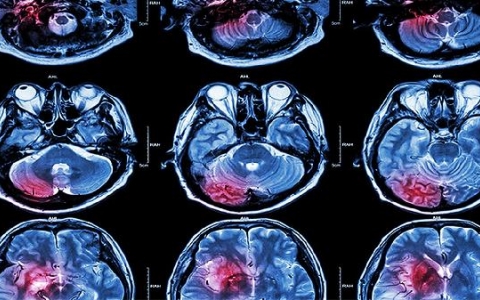

脑溢血有什么症状?

脑溢血也叫脑出血,这也是一种自发性出血,脑溢血是一种比较严重的疾病,很多人想知道脑溢血有什么症状。临床上,脑溢血的症状和出血的部位有很大关系,不同类型的脑溢血症